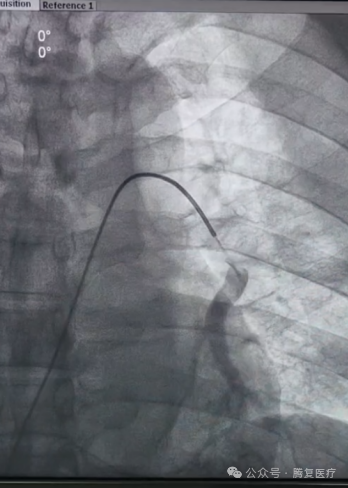

患者仰卧位,局麻后经股静脉穿刺放置血管鞘,引入导丝和导管,建立右心房-右心室-肺动脉通路。韩宝石教授团队将Tendvia®血栓抽吸导管,沿导丝推送至肺动脉。管口贴近血栓处停止,撤出导管芯。并将Tendvia®肺动脉血栓取支架沿导丝通过抽吸导管向前推送,精确导入到患者的肺动脉血栓部位。再回撤输送鞘管,支架自动膨开。连接抽吸器并形成负压,回撤取栓支架的同时旋转开关释放负压。最后,Tendvia®肺动脉取栓支架捕获和收集血栓进入抽吸导管,经负压抽吸同步的作用下,顺利为患者取出了血栓。

手术极大地改善了患者的肺动脉血流和氧合情况,手术圆满成功。全程手术时间约60分钟,患者术后各监测指标平稳,安返病房。